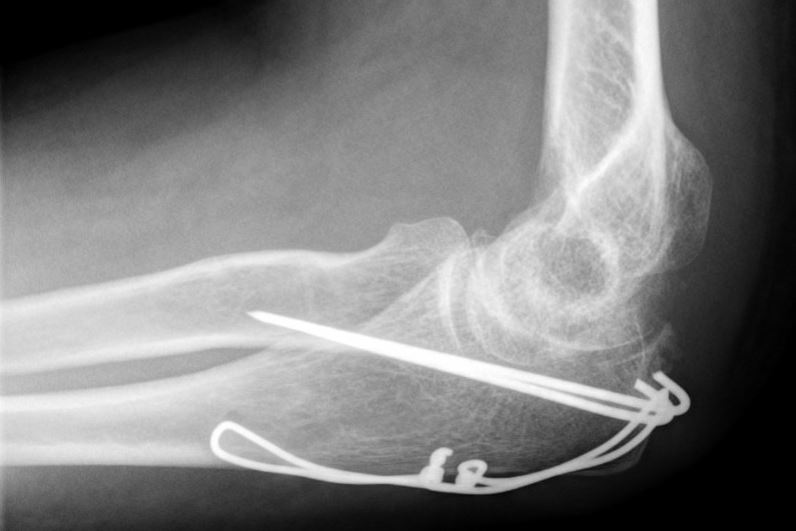

De meeste breuken van het olecranon zullen operatief worden vastgezet met een zogenaamde ‘Zuggurtung’, bestaande uit enkele dunne metalen pinnetjes en een metalen vlechtdraad. Deze worden geplaatst via een snede aan de strekzijde van de elleboog. Wanneer de breuk uit meerdere delen bestaat, kan het ook zijn dat de traumachirurg er voor kiest de breuk vast te zetten met een plaat en schroeven. Welke operatie u krijgt, is dus afhankelijk van de eigenschappen van de breuk en de toestand van de huid en de spieren, maar ook de voorkeur van uw traumachirurg.